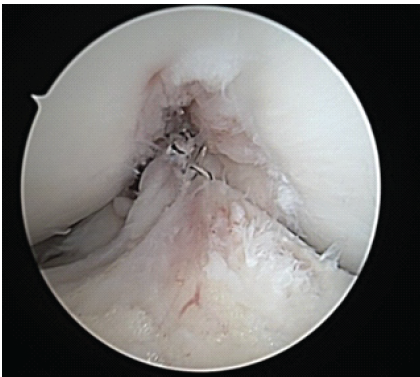

An arthrex fiberloop was placed. With secure fixation on the femoral and tibial stumps, the patient had ACL repair performed in extension and had sutures tied with secure fixation with the aid of a knot pusher. The knot was small and did not impinge in the notch. The patient had a stable ACL to probing and had an excellent endpoint to a gentle Lachman’s at 30° of knee flexion and no impingement along the lateral wall or notch in full extension. Multiple photographs were taken documenting and demonstrating the ACL repair (Figs. 6, 7, 8).

Figure 6: Arthroscopic image of right knee anterior cruciate ligament repair from anterolateral portal at 90° of flexion. Note the limited space for proximal femoral stump suture placement.